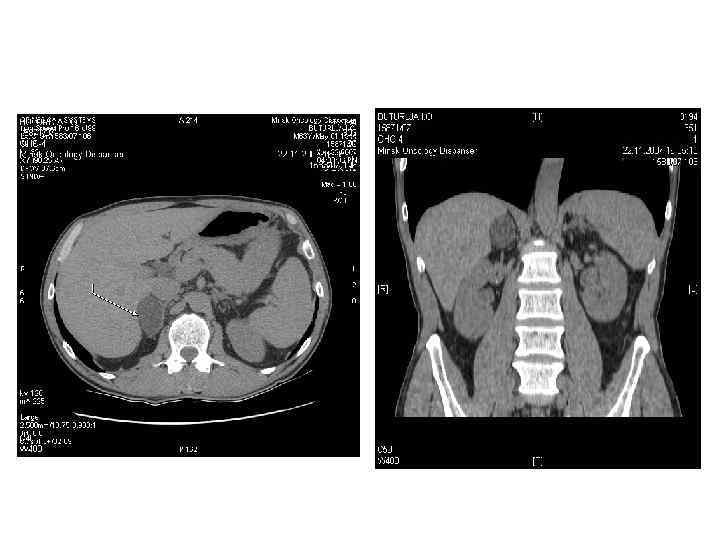

Диагностика • Методы визуализации надпочечников: 1) КТ 2) МРТ 3) ПЭТ 4) Ультразвуковое исследование • Клиническая картина • Гормональное обследование • Пункционная биопсия

КТ и МРТ признаки ДОНП АКР Метастаз Размер < 3 см > 4 см < 3 см (обычно) Форма Округлая, четкий контур Неправильная, нечеткий контур Овальная; нечет- кий, прерывистый контур Сторона выявления Одиночная или двусторонняя Чаще двусторонний Рост < 1 см в год > 2 см в год Различный Структура Гомогенная Гетерогенная, с участками различной плотности Гетерогенная с участками различной плотности

КТ и МРТ признаки (2) ДОНП АКР Метастаз < 10 HU >10 -25 HU Васкуляризация в контрастную фазу + + Изменение плотности через 10 минут выведения контраста >50% <50% Некрозы, кальцинаты, кровоизлияния Редко Часто Не всегда Неконтрастная плотность «Инциденталома надпочечника. Методические рекомендации для врачей первичного звена» под редакцией Дедова И. И. , Мельниченко Г. А.